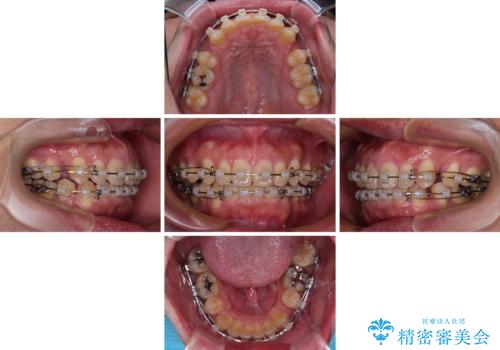

- クリアブラケット

- 口が閉じられないとのことで来院された患者様です。

顎先に力を入れないと唇が閉じきれない口元であったので、上下左右の第一小臼歯4本を抜歯して、ワイヤー装置にて矯正治療を行うこととしました。

2年から2年半の治療期間を想定しており、予定通りの期間で無事に終了することができました。